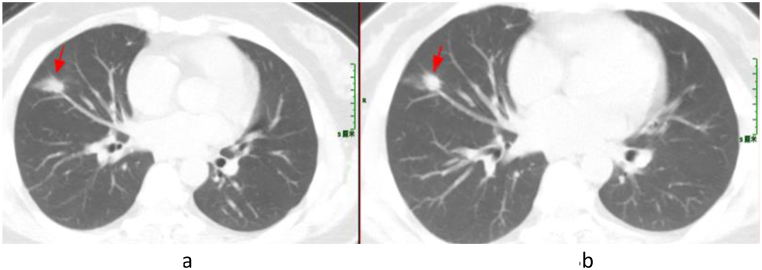

Following a diagnosis of pneumonia caused by TW infection, a treatment plan consisting of ceftriaxone followed by compound sulfamethoxazole was formulated for Patient 3. However, the patient refused intravenous ceftriaxone and was discharged from the hospital. Subsequently, Patient 3 changed to take TMP-SMZ orally. After twenty days, the patient developed gastrointestinal reactions, and discontinued taking the medicine independently. Despite no significant change (Fig. 3(a and b)) indicated by chest CT scan one year later, Patient 3 experienced intermittent cough, recurrent joint pain and diarrhea, and reported joint pain on September 7, 2022. MRI examination of both hips revealed a small amount of fluid in the left hip joint of this patient (Fig. 4).

Fig. 3.

Chest CT Scan of Patient 3 (The dates from left to right are April 16, 2021 (a) and May 21, 2022 (b)). The arrowhead shows the focus.

Fig. 4.

MRI of both hips of Patient 3. The arrowhead shows the focus.